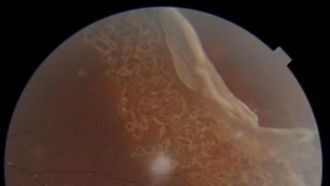

- When a 13-year-old boy from India suffered a severe eye injury due to being hit by a cricket ball, he was rushed to Aster Clinic Bur Du...

- Aster Hospital Mankhool recently restored the vision of Dhikshit Kottiyattil Anoop, a 15-year-old Indian student. Dhikshit suffered a s...

- In a groundbreaking medical achievement, Aster Hospital Al Qusais has successfully performed an ocular prosthesis surgery on a 42-year-...